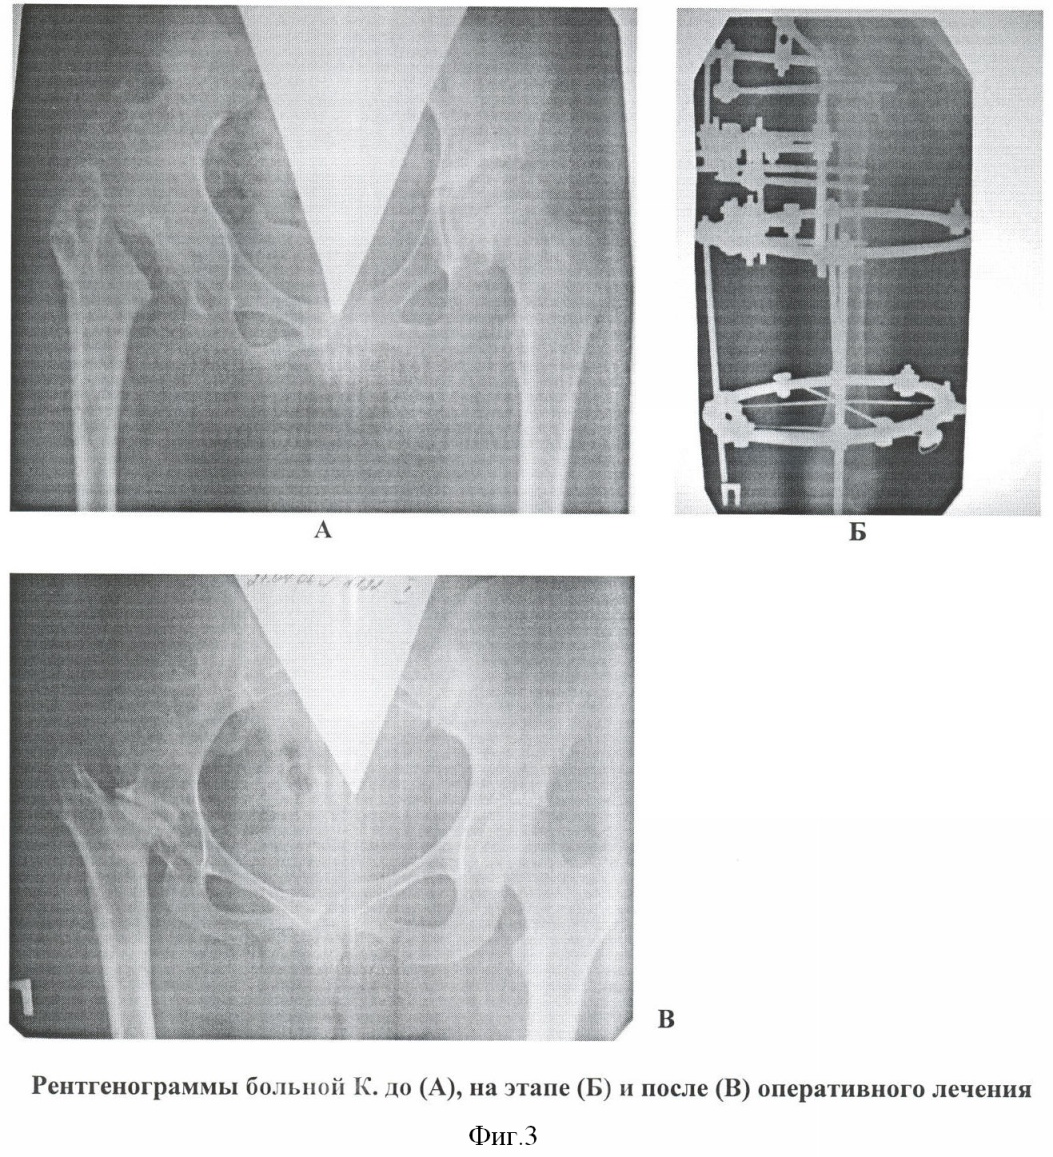

Способ применен при лечении больных К., 10 лет, история болезни 991845 и Г., 12 лет, история болезни 060836. Получен хороший функциональный результат.